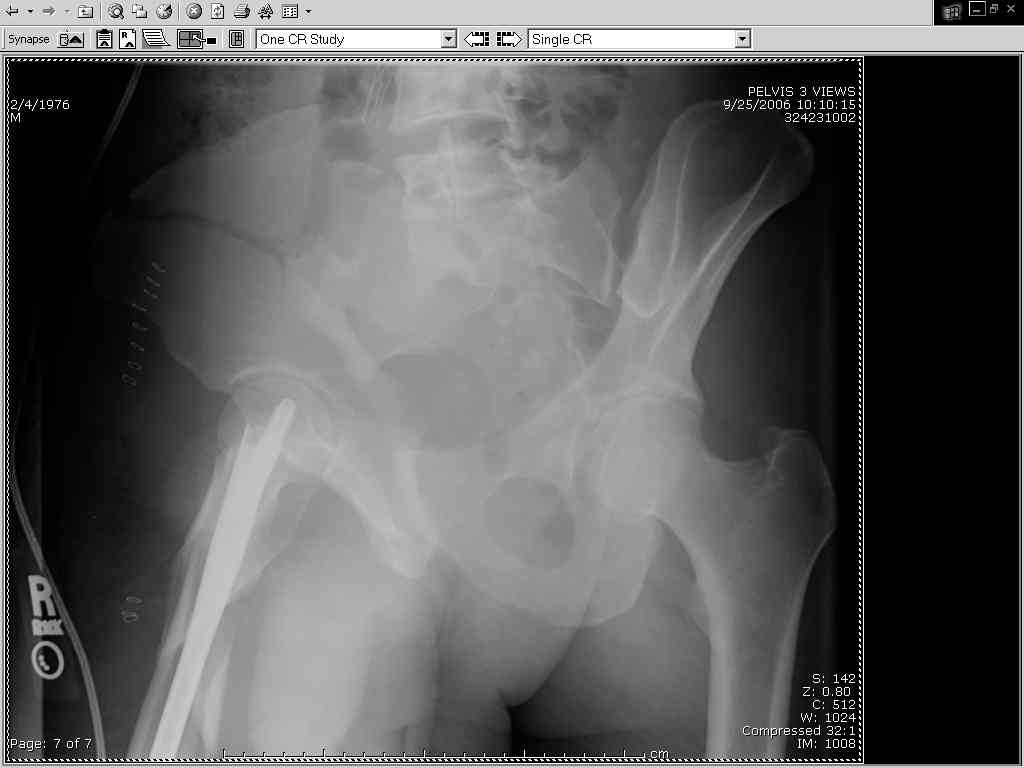

It almost looks to me like an extra-articular both column fx, in addition to the pelvic component. It has the typical triangular fragment and the OO view has a hint of the spur. You may be able to get it all with plates. I would consider fixing the crest first, then a long plate for both symph and iliac portion. SI may close with reduction of symphisis. Looks like the inferior portions are intact. I like your plan as well. You will probably solicit lots of opinion. Good luck. Look forward to post op view.

Thanks Adam - I agree it's not a pure APC (is there really such thing as a pure force vector strictly in the x,y or z plane?). I stand corrected. Maybe a hybrid APC (ext rot of L hemipelvis, symphysis disruption, ext rot of R anterior innominate) plus vertical shear as well with 3 or-so cm of cephalad migration of the R ilium. Maybe just "C-type".....